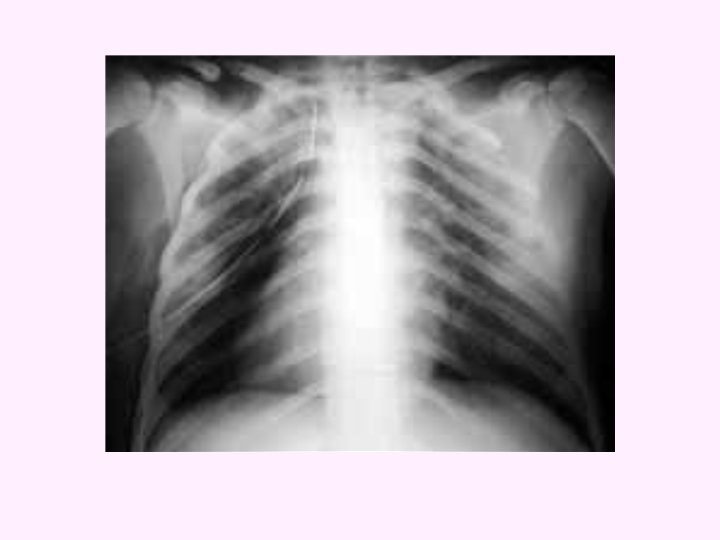

PNÖMOTORAKS Plevral boşluğa hava toplanmasıdır.

Kapalı Pnömotoraksta Atmosfer havası bronş, bronşiyal yada alveol gibi solunumla ilgili internal yapılardan plevral alan girer ancak çıkmaz.

KAPALI PNÖMOTORAKS